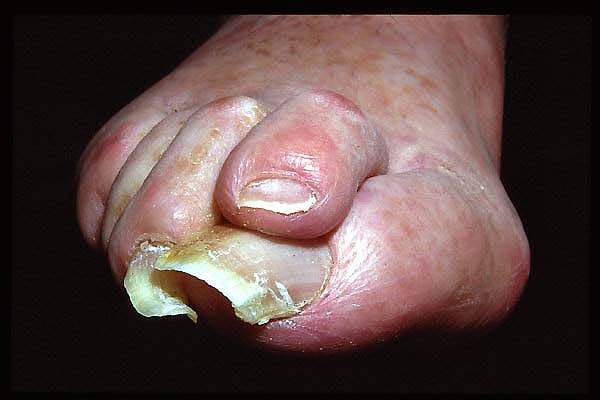

Semiavulsión de uña distrófica